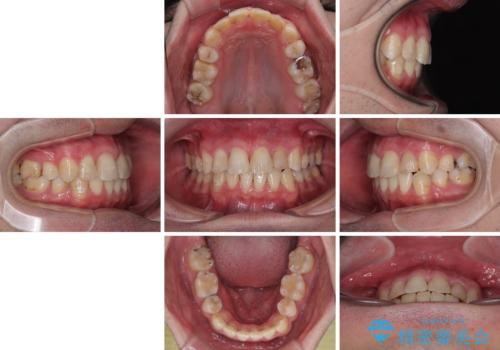

2年半の治療期間を想定しており、予定通りの期間で無事に終了することができました。

唇や顎先に力を入れないなくてもスムーズに唇を閉じることができるようになりました。